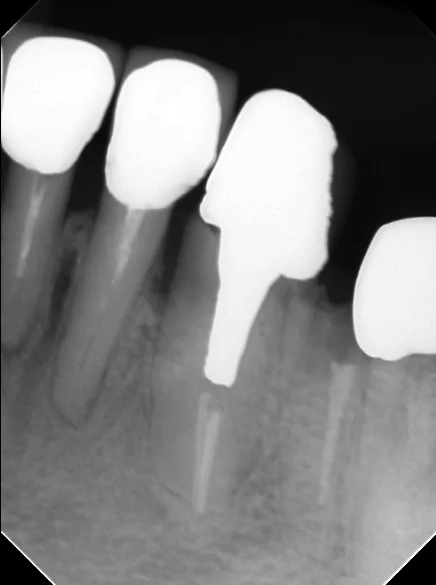

中心結節破折が原因で起こった神経の壊死を放置して、外部吸収が起こったケース

中心結節破折が原因で起こった神経の壊死を放置して、外部吸収が起こったケース